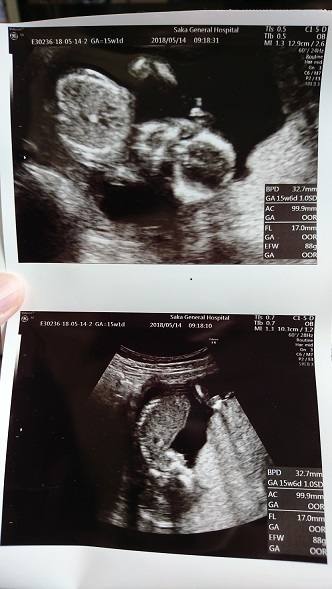

11週3日(11w3d・性別不明)|345 さん(35歳)

エコー写真撮影時のエピソード:

初めて主人付き添いでの健診。ぴょこんぴょこん跳ねたり伸びたり元気な赤ちゃんが見れました。

お医者さんも、「今日はパパも居るからご機嫌だね~。」って言ってくれてとても暖かい気持ちになりました。 写真は何枚か撮っていただいた中の顔が写っているものです。 手を顔の横に置いて寝ている姿は主人そっくり。 会えるのが楽しみです。